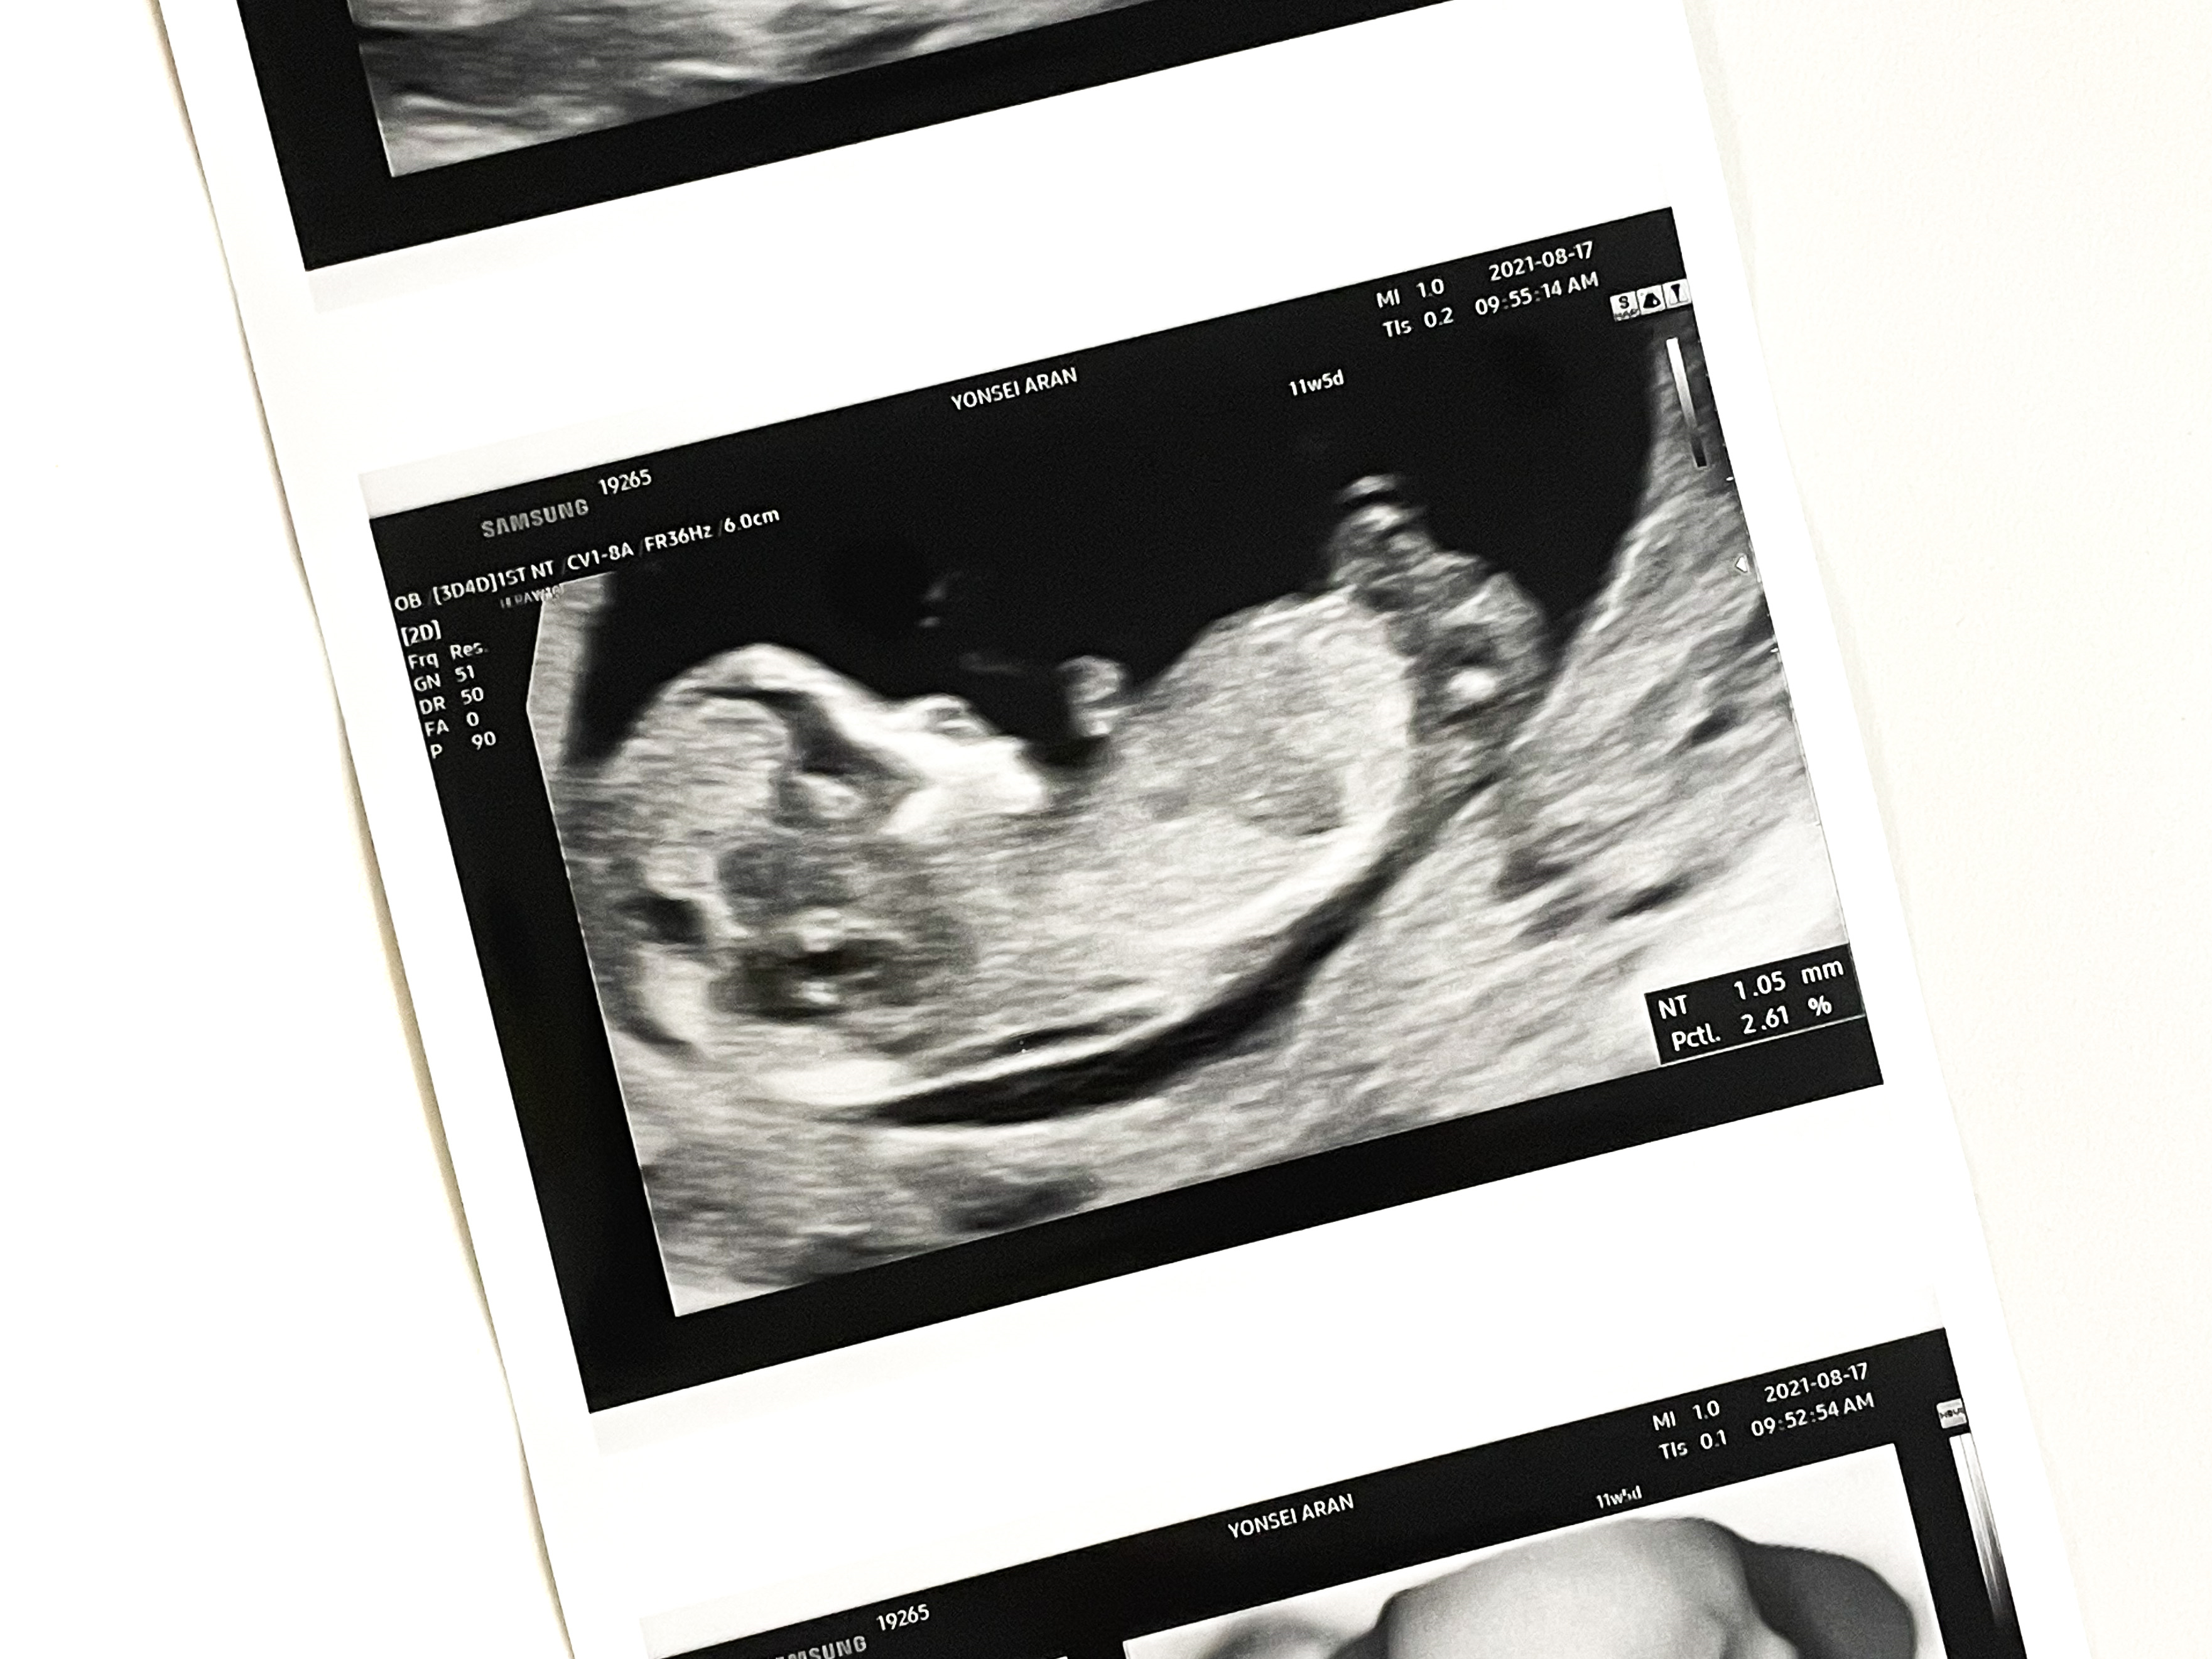

11주 5일

1차 기형아 검사를 받으러 갔다.

목투명대 검사

첫 검사는 정밀 초음파 검사실에서 이루어지는 목투명대 검사였다.

목투명대 길이 정상범위는 3mm 미만인데 1.05mm가 나왔다.

그리고 주수에 맞게 잘 크고 있었다.

비어있던 머리 공간도 어느새 나비가 자리잡고 있었다.

입체 초음파도 찍어주셨다.